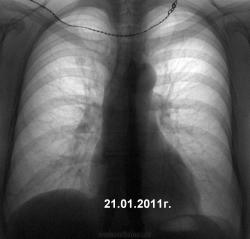

растет относительно быстро, контуры не очень ровные, наиболее вероятно доброкачественная опухоль (рак уже засеял-бы за период такого спокойного ожидания!!!!). однозначно необходима томография или линейная или спиральная. в нашем заведении в таких ситуациях обязательна боковая проекция, консультация торакального онкохирурга

растет относительно быстро, контуры не очень ровные, наиболее вероятно доброкачественная опухоль (рак уже засеял-бы за период такого спокойного ожидания

!!!!). однозначно необходима томография или линейная или спиральная. в нашем заведении в таких ситуациях обязательна боковая проекция, консультация торакального онкохирурга

Ставила бы под вопросом и туберкулому, и онко. У нас система такая - отправляешь к онкологам, они переправялют фтизиатрам. Пока фтизиатры не обследуют с такой тенюшкой, не проведут своего лечения, пока пациента после этого лечения в области не прокунсультируют и не скажут, что "Да, это онко!" - онкологи на себя ничего не возьмут.Поэтому выкручиваемся так: "Заболевание пр.легкого? Туберкулома? Дообслед: снимок верхушек спиной или по Флейшнеру (при необходимости), томограммы, еще лучше если КТ. Конс. фтиз, онк. И ждем результата. В 2009 г. сделала бы снимок спиной. Если бы тень осталась (не расправилась бы на сосуды), тогда бы "живым" пациента бы не отпустила. А так, честно говоря, могла бы в 2009 г.пройти мимо.

Однозначно растёт, но вряд ли туберкулома. И направлять лучше в онкодиспансер с прицелом на рак, а то вдруг в тубдиспансере не разберутся.